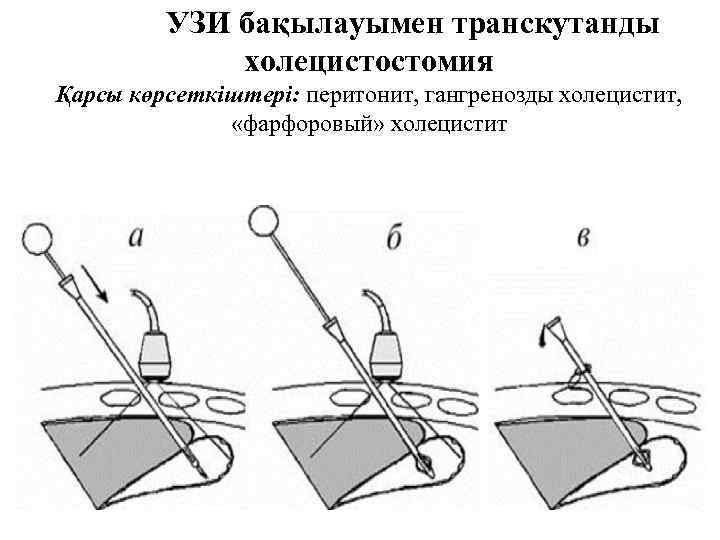

УЗИ бақылауымен транскутанды холецистостомия Қарсы көрсеткіштері: перитонит, гангренозды холецистит, «фарфоровый» холецистит